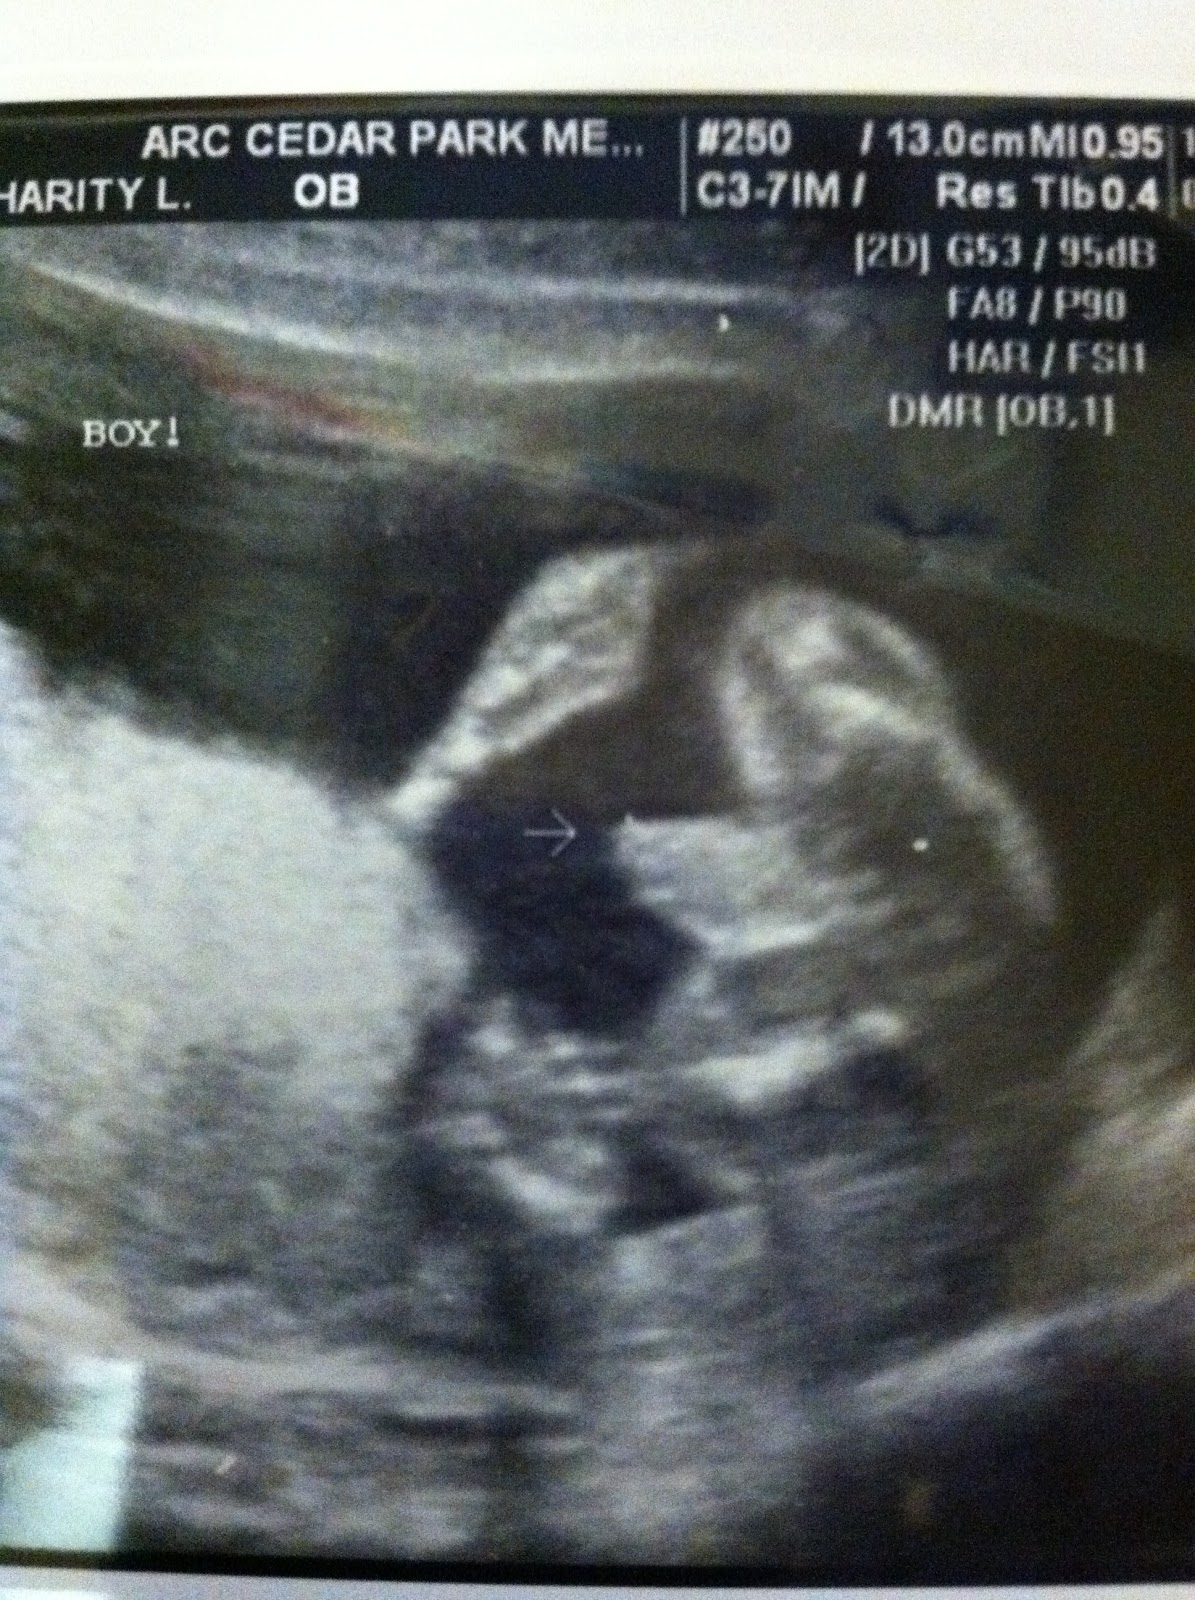

It's a boy!

We had our 20-week ultrasound last week and everything looks great! 4 chambers to the heart (yay!), normal spine, normal mouth/nose, normal belly. Growing well at 13oz already (just short of a pound). And....he's a boy!

The arrow points to his, well, boy parts. :)